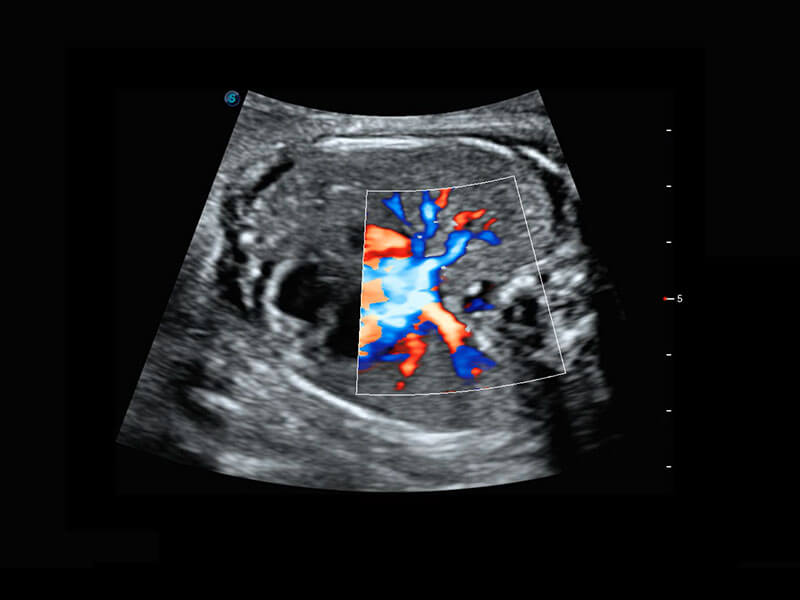

胎心筛查

P60搭载一系列胎儿心脏成像技术,实现精细的胎儿心脏评估。

• 四腔心血流

• 右室双出口